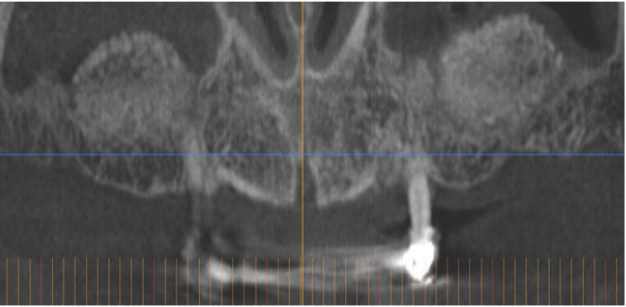

Diabetic patients have shown more severe periodontal disease than healthy control groups, especially when poor glycemic control is present Figure 2 shows a diabetic individual with severe periodontal disease, teeth are longer with increased mobility and migrations, roots are exposed and inflammatory signs can be observed in the gingival (edema, redness and bleeding). We also can see extreme bone destruction around teeth in X-rays from Figure 3 (bone should be 1,5mm below the enamel of the crown). One hypothesis to explain this damage in the periodontal tissues states that advanced glycosylation end products that appear in diabetic patients due to the hyperglycemia make the immune system hyperreactive to dental plaque, increasing destruction of periodontal support [1-3].

Figure 3: Patient 1: Periodontal destruction showed by periapical X-ray.

Figure 4: Patient 2: Computerized tomography of a diabetic subject that will lose all the teeth due to periodontal disease. The reduced bone in the upper posterior areas can be observed.